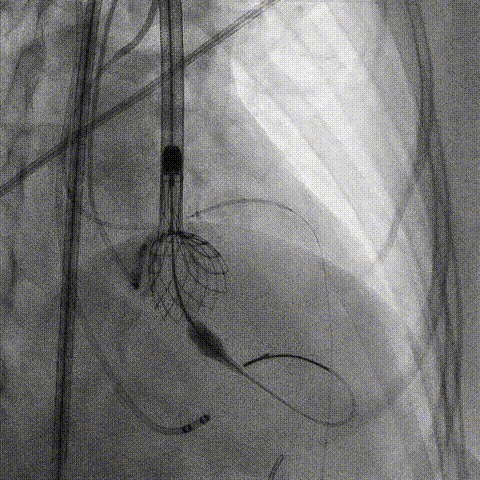

第一次释放

再次评估左冠开口,考虑调整瓣膜深度

回收后调整深度,再次释放

评估左冠开口

左冠开口切线位造影

决定左冠烟囱支架保护冠脉

调整支架位置

释放冠脉支架

释放瓣膜